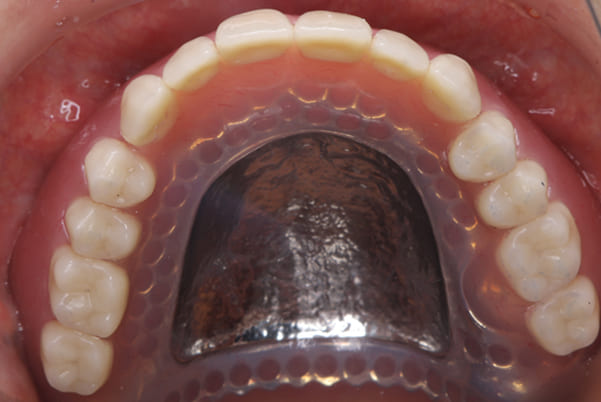

上顎治療後

精密な型どりは、通常保険治療では使用しない、この患者様だけに合った型を取るトレーを作製、また寸法変化の最も少ない精密なシリコンを用いてお口の中を精密に限りなく再現する型どりの方法で型をお取りしました。

完成前に適合や見た目のチェックでは、咬む力で義歯がたわみ、残りの歯に負担がかからないよう、見えない内側は、金属を用い、強度を増し、また金属のため薄くすることで違和感をなくす設計とし、完成前に試し合わせを行い、装着感、審美性を確認しました。